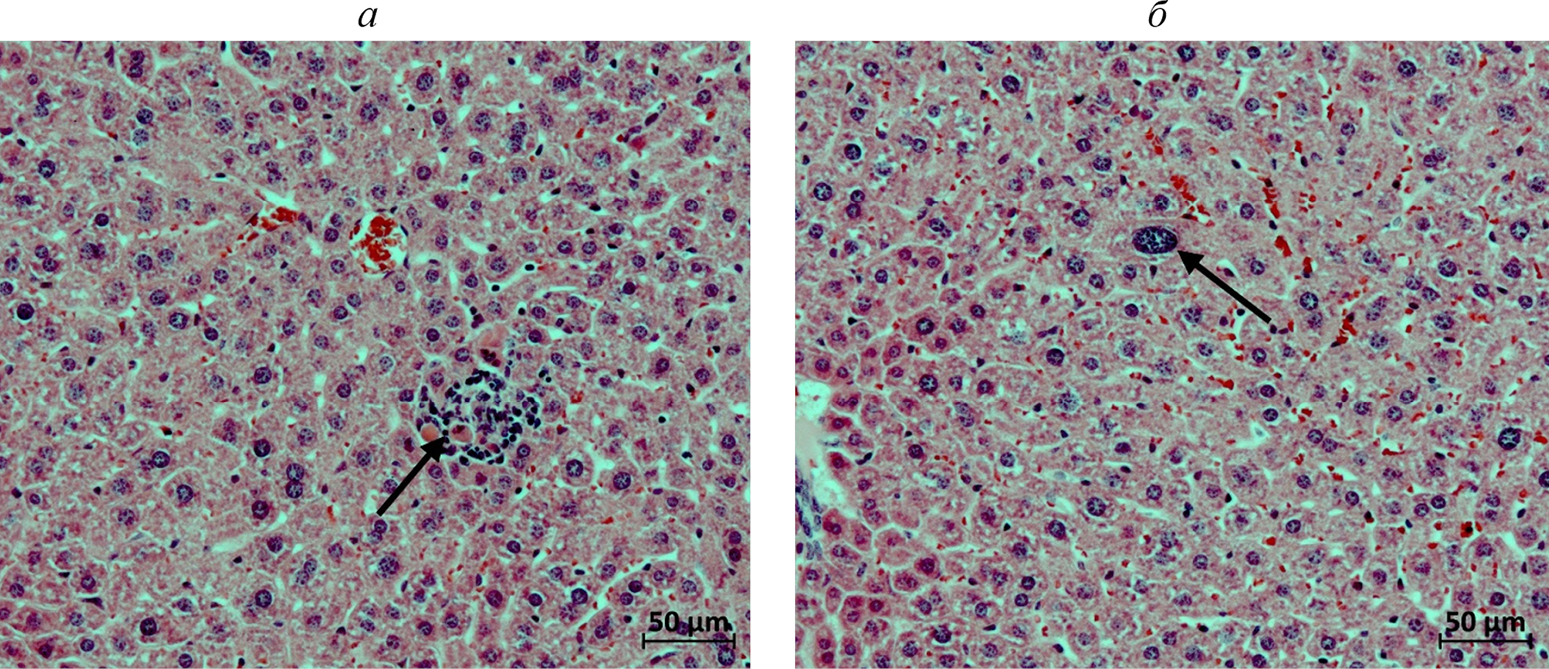

Острая токсичность. Печень. У мышей контрольной группы на 7-й день после однократного введения физраствора в паренхиме печени находили единичные мелкие очаги мононуклеарной инфильтрации (рис. 2а). В одном случае отмечали очаговую гипертрофию гепатоцитов (рис. 2б). В группе введения однократной дозы препарата практически у всех животных в печеночной паренхиме обнаруживали многочисленные мелкие очаги мононуклеарной инфильтрации на месте погибших гепатоцитов с поздними проявлениями их фагоцитоза (рис. 3а) (табл. 2). У двух мышей данной группы отмечали очаговую гипертрофию гепатоцитов, у одной – единичные случаи кариомегалии гепатоцитов (рис. 3б). В группе введения пятикратной дозы препарата у двух животных в печеночной паренхиме находили также немногочисленные очаги нейтрофильной инфильтрации (рис. 4а), еще в двух случаях в очагах мононуклеарной инфильтрации присутствовали сегментоядерные лейкоциты (рис. 4б). В группе введения 10-кратной дозы препарата в печени встречали те же изменения, что и при введении тестируемого вещества в дозировке ×5. Вместе с тем, у двух животных данной группы в печени находили мелкие свежие очаги гепатоцитов с начальными явлениями некроза (рис. 5а). Еще у одной мыши в одной из долей органа наблюдали единичные гепатоциты с пигментными включениями в цитоплазме (рис. 5б).

Рис. 2. Фрагменты печени самок мышей контрольной группы. Окраска гематоксилином и эозином. Стрелками указаны: а – мелкий очаг мононуклеарной инфильтрации в паренхиме одной из долей органа (мышь 5.1); б – гипертрофия отдельных гепатоцитов (мышь 5.2).

Рис. 3. Фрагменты печени самок мышей на 7-й день после однократного введения 1.5 Ед С115Н-PIC-сом МГЛ/2 мг метиина. Окраска гематоксилином и эозином. Стрелками указаны: а – мелкий очаг мононуклеарной инфильтрации в паренхиме одной из долей органа (мышь 1.2); б – кариомегалия гепатоцита (мышь 1.3).